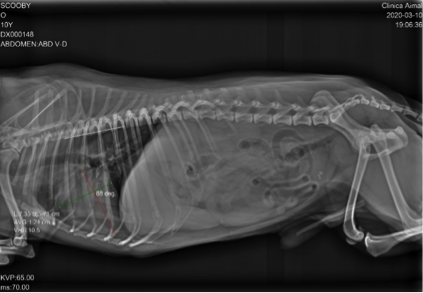

Después de revisar completamente a Scooby, nos cercioramos del fuerte dolor abdominal que efectivamente presenta. La auscultación es aparentemente normal y su temperatura de 38,4ºC. Se le recomienda la realización de radiografías de abdomen y columna (para descartar una posible discoespondilitis).

Observamos que la columna es aparentemente normal, pero podemos ver urolitos en la vejiga de la orina.